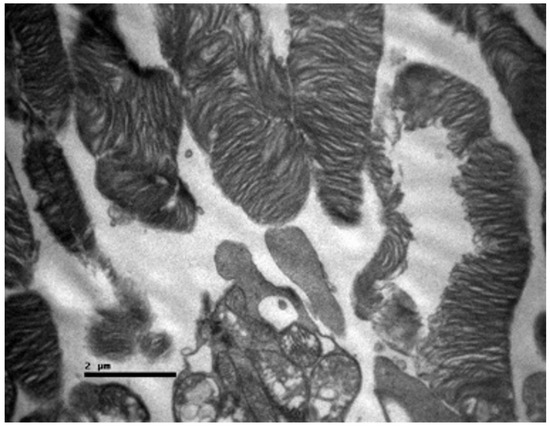

Background/Objectives: Cisplatin is a potent chemotherapeutic agent whose clinical utility is limited by severe side effects, including neurotoxicity affecting the ocular system. The pathophysiology involves oxidative stress and mitochondrial dysfunction, to which the retina is particularly vulnerable. Selenium (Se), an essential trace element and component of antioxidant enzymes, has shown potential in mitigating cisplatin toxicity, although its efficacy with respect to retinal structure and the influence of administration routes remain underexplored. This study aimed to evaluate the protective efficacy of selenium against cisplatin-induced retinal toxicity and compare the effects of intraperitoneal and oral selenium administration. Methods: Forty adult male Wistar rats were randomized into four groups (n = 10 each): Group A (Cisplatin Monotherapy, 3.5 mg/kg IP for 5 days; cumulative dose 17.5 mg/kg); Group B (Cisplatin + Intraperitoneal Selenium, 2.73 mg/kg; cumulative dose 60 mg/kg); Group C (Control); and Group D (Cisplatin + Oral Selenium). Selenium prophylaxis, administered as sodium selenite (Na2SeO3), began two days prior to cisplatin administration and continued for 15 days post-treatment. Retinal evaluation two weeks after cisplatin cessation included light microscopy, semi-quantitative immunohistochemical (IHC) analysis for inflammatory (IL-6) and fibrotic (TGF-β2) markers, and Transmission Electron Microscopy (TEM) for ultrastructural analysis, which were the primary endpoints. Statistical differences in the IHC scores were analyzed via the Kruskal‒Wallis H test with Dunn’s post hoc comparisons. Results: Cisplatin monotherapy (Group A) caused severe disruption of the retinal architecture, including edema, reactive gliosis, and significant upregulation of IL-6 and TGF-β2. Ultrastructural analysis revealed mitochondrial swelling (cristolysis) and photoreceptor disk fragmentation. Intraperitoneal selenium (Group B) was associated with significant structural preservation and intact mitochondria, with TGF-β2 levels comparable to those of the controls, although the IL-6 level remained moderately elevated. Conversely, oral selenium (Group D) suppressed both IL-6 and TGF-β2 expression to near-negative levels but provided less ultrastructural protection, resulting in persistent mitochondrial swelling and focal photoreceptor disruption. Conclusions: Systemic cisplatin induces severe subcellular retinal toxicity characterized by mitochondrial damage and photoreceptor degeneration. Selenium supplementation attenuates these effects; however, outcome patterns differ by administration route. Intraperitoneal selenium was associated with greater morphological and ultrastructural preservation despite persistent IL-6 elevation, whereas oral selenium normalized immunohistochemical marker expression to near-control levels but was associated with more pronounced residual subcellular damage on qualitative TEM assessment. These preliminary morphological and immunohistochemical findings suggest that the route of selenium delivery may influence its neuroprotective profile; however, pharmacokinetic measurements and functional retinal assessments, such as electroretinography, are warranted before its clinical translation. Full article